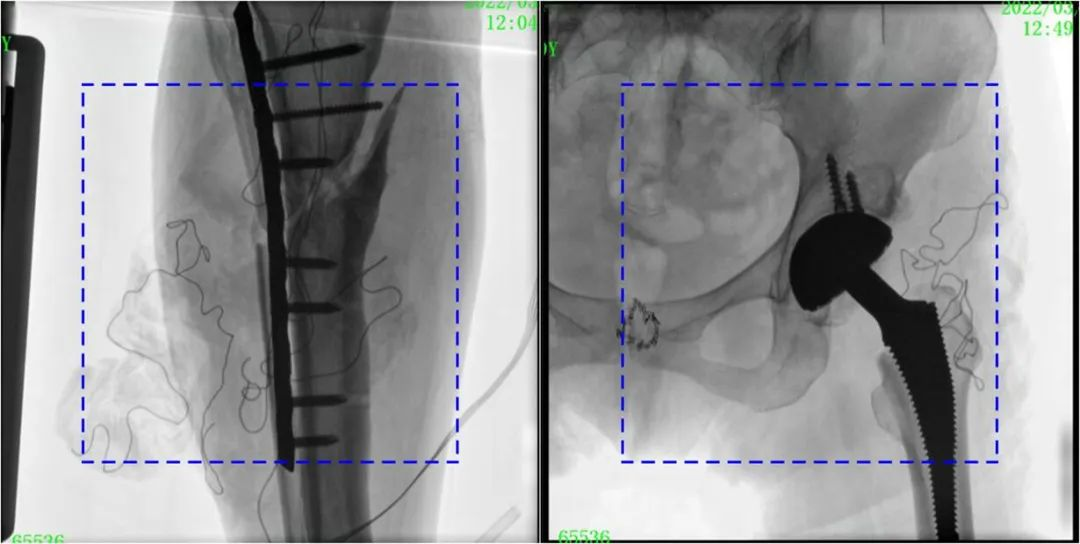

與傳統(tǒng)的21CM×21CM成像尺寸相比,普愛(ài)醫(yī)療大平板一體式C形臂具有30CM×30CM更大成像尺寸,能夠一次成像5.5節(jié)椎體,呈現(xiàn)更全面的影像信息,即便是手術(shù)經(jīng)驗(yàn)不豐富的年輕醫(yī)生也能通過(guò)圖像迅速判斷椎體節(jié)段、定位手術(shù)部位,避免因?yàn)橐曇安蛔愣斐傻亩啻味ㄎ?、反?fù)曝光,提高效率的同時(shí)避免過(guò)量攝入輻射。

普愛(ài)醫(yī)療大平板一體式C形臂圖像與傳統(tǒng)圖像對(duì)比(藍(lán)色虛線內(nèi)為傳統(tǒng)21CM×21CM平板的成像區(qū)域)